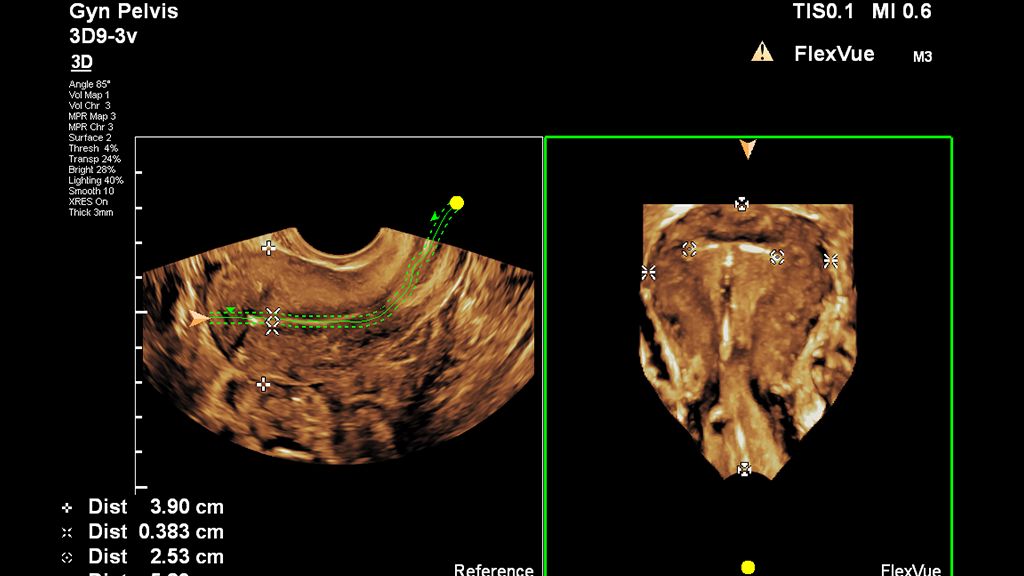

95% of OB/GYN users surveyed feel that FlexVue with Orthogonal View may improve their workflow [1].

• FlexVue with Orthogonal View with quantification allows greater flexibility in plane acquisition from 3D datasets and provides a comprehensive measurement package.

• Ultrasound system screen capture of FlexVue measurements

FlexVue image of the uterus with measurements

• Uterine ultrasound image in coronal plane using FlexVue

Visualize challenging OB/GYN anatomy with ease

FlexVue supports assessment of OB/GYN anatomy and pathology with easy visualization of technically difficult anatomical views within 3D volumes.